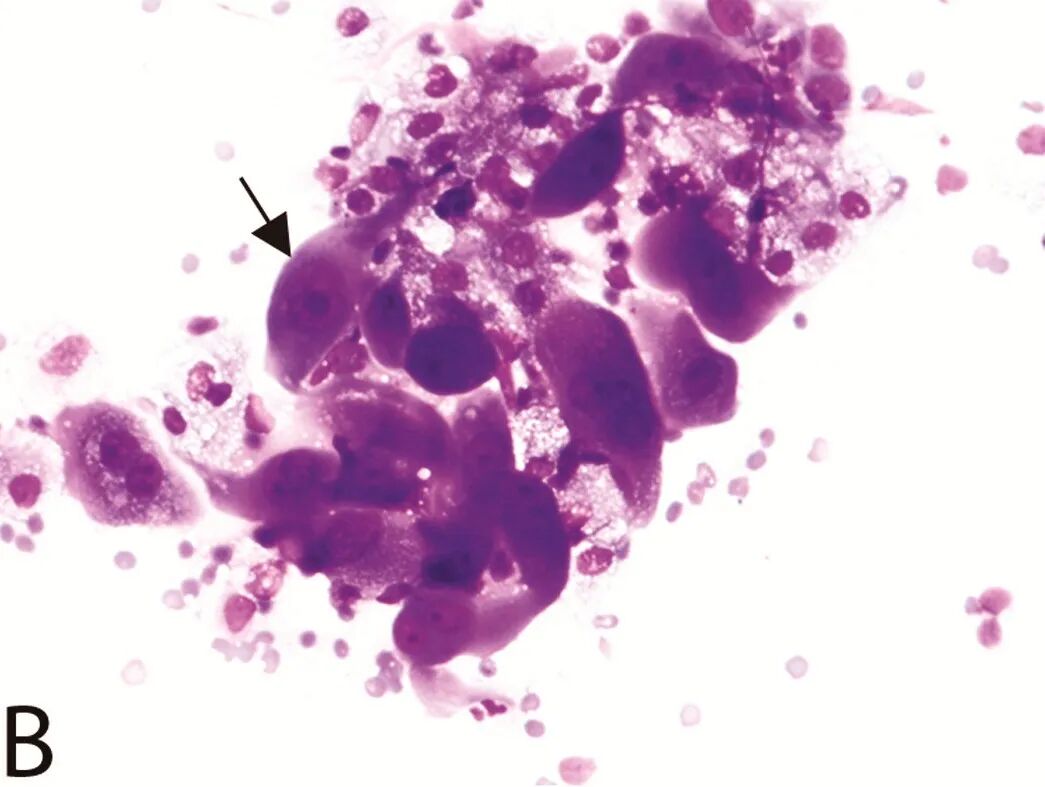

图B. 与图A同一粗针活检组织的细胞学印片,显示较多增大的上皮样细胞(与相邻的红细胞比较)与泡沫样组织细胞的聚集体。核仁增大在某些细胞中非常明显。捏长的外观在许多细胞中保存完好(箭头)